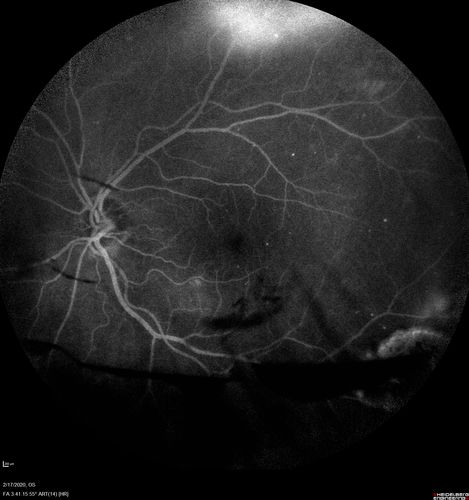

PDR and Vitreous Hemorrhage - High Risk Left Eye - Low Risk Right Eye

50 year old man with type I diabetes mellitus for 26 years. New Vitreous Hemorrhage in the left eye. Both eyes have NVE. Both also have foveal hypoplasia

Vitreous Hemorrhage and Proliferative Diabetic Retinopathy - Low risk right eye - High Risk Left Eye - Also Fovea Plana